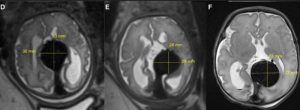

کاهش اندازه ناهنجاری از چپ به راست بعد از انجام عمل: